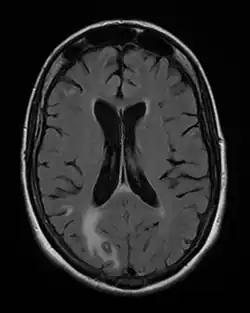

On décrit de rares cas où un sujet VIH+, sans immunité anti-toxoplasmique (pas de contact antérieur) contracte une toxoplasmose, mais le plus souvent il s'agit de patients immunisés contre la toxoplasmose, donc porteurs de kystes qui réactivent l'infection lors d'une baisse conséquente de leurs défenses immunitaires ; généralement, ils présentent une toxoplasmose cérébrale.

La toxoplasmose cérébrale est une maladie opportuniste dont la survenue chez les personnes séropositives marque l'évolution de l'infection par le VIH au stade de sida. Elle survient en règle générale chez des sujets séropositifs au VIH, ayant moins de 200 lymphocytes T CD4+, avec une sérologie toxoplasmique positive et ne recevant pas de prophylaxie spécifique. C'est alors que les bradyzoïtes libèrent les tachyzoïtes qui essaiment dans tout le corps via le système sanguin[37]. En 2008 en France, la toxoplasmose cérébrale représentait 12 % des personnes qui découvraient leur séropositivité au VIH après le déclenchement d'une affection opportuniste[38].

- il s'agit d'un (ou de plusieurs) abcès cérébral (cas le plus fréquent) donnant un tableau neurologique rapidement progressif. Les signes cliniques dépendent de la localisation de(s) l'abcès : hémiplégie ou hémiparésie, syndrome cérebelleux, aphasie, amputation du champ visuel, ou signes plus diffus à type de somnolence, désorientation, crises comitiales ;